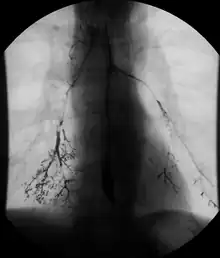

Enteroclysis

Enteroclysis is also known as small bowel enema.[21] It has been largely replaced by magnetic resonance enterography/enteroclysis[13] and computed tomography enterography/enteroclysis.[22]

In addition to fasting for 8 hours prior to examination, a laxative may also be necessary for bowel preparation and cleansing.[12] The main aim of this study is to distend the proximal bowel through infusion of large amount of barium suspension. Otherwise, the distension of distal small bowel is generally similar with small bowel follow-through. Therefore, there is a need to pass a tube through the nose into the jejunum (nasojejunal tube) to administer large amount of contrast. This can be unpleasant to the subject, requires more staff, longer procedural time, and higher radiation dose when compared to small bowel follow-through. The indications for enteroclysis are generally similar to small bowel follow-through. Barium suspensions such as diluted E-Z Paque 70% and Baritop 100% can be used. After that, 600 ml of 0.5% methylcellulose is administered after 500 ml of 70% barium suspension is given. Bilbao-Dotter tube and Silk tube can be used to administer barium suspension. The subject should be fasted overnight, any antispasmodic drugs should be stopped one day before the examination, and Tetracaine lozenges can be used 30 minutes before the procedure to numb the throat for nasojejunal tube insertion.[13]

The filling of the small intestines can be viewed continuously using fluoroscopy, or viewed as standard radiographs taken at frequent intervals. The technique is a double-contrast procedure that allows detailed imaging of the entire small intestine. However, the procedure may take 6 hours or longer to complete and is quite uncomfortable to undergo.[23]